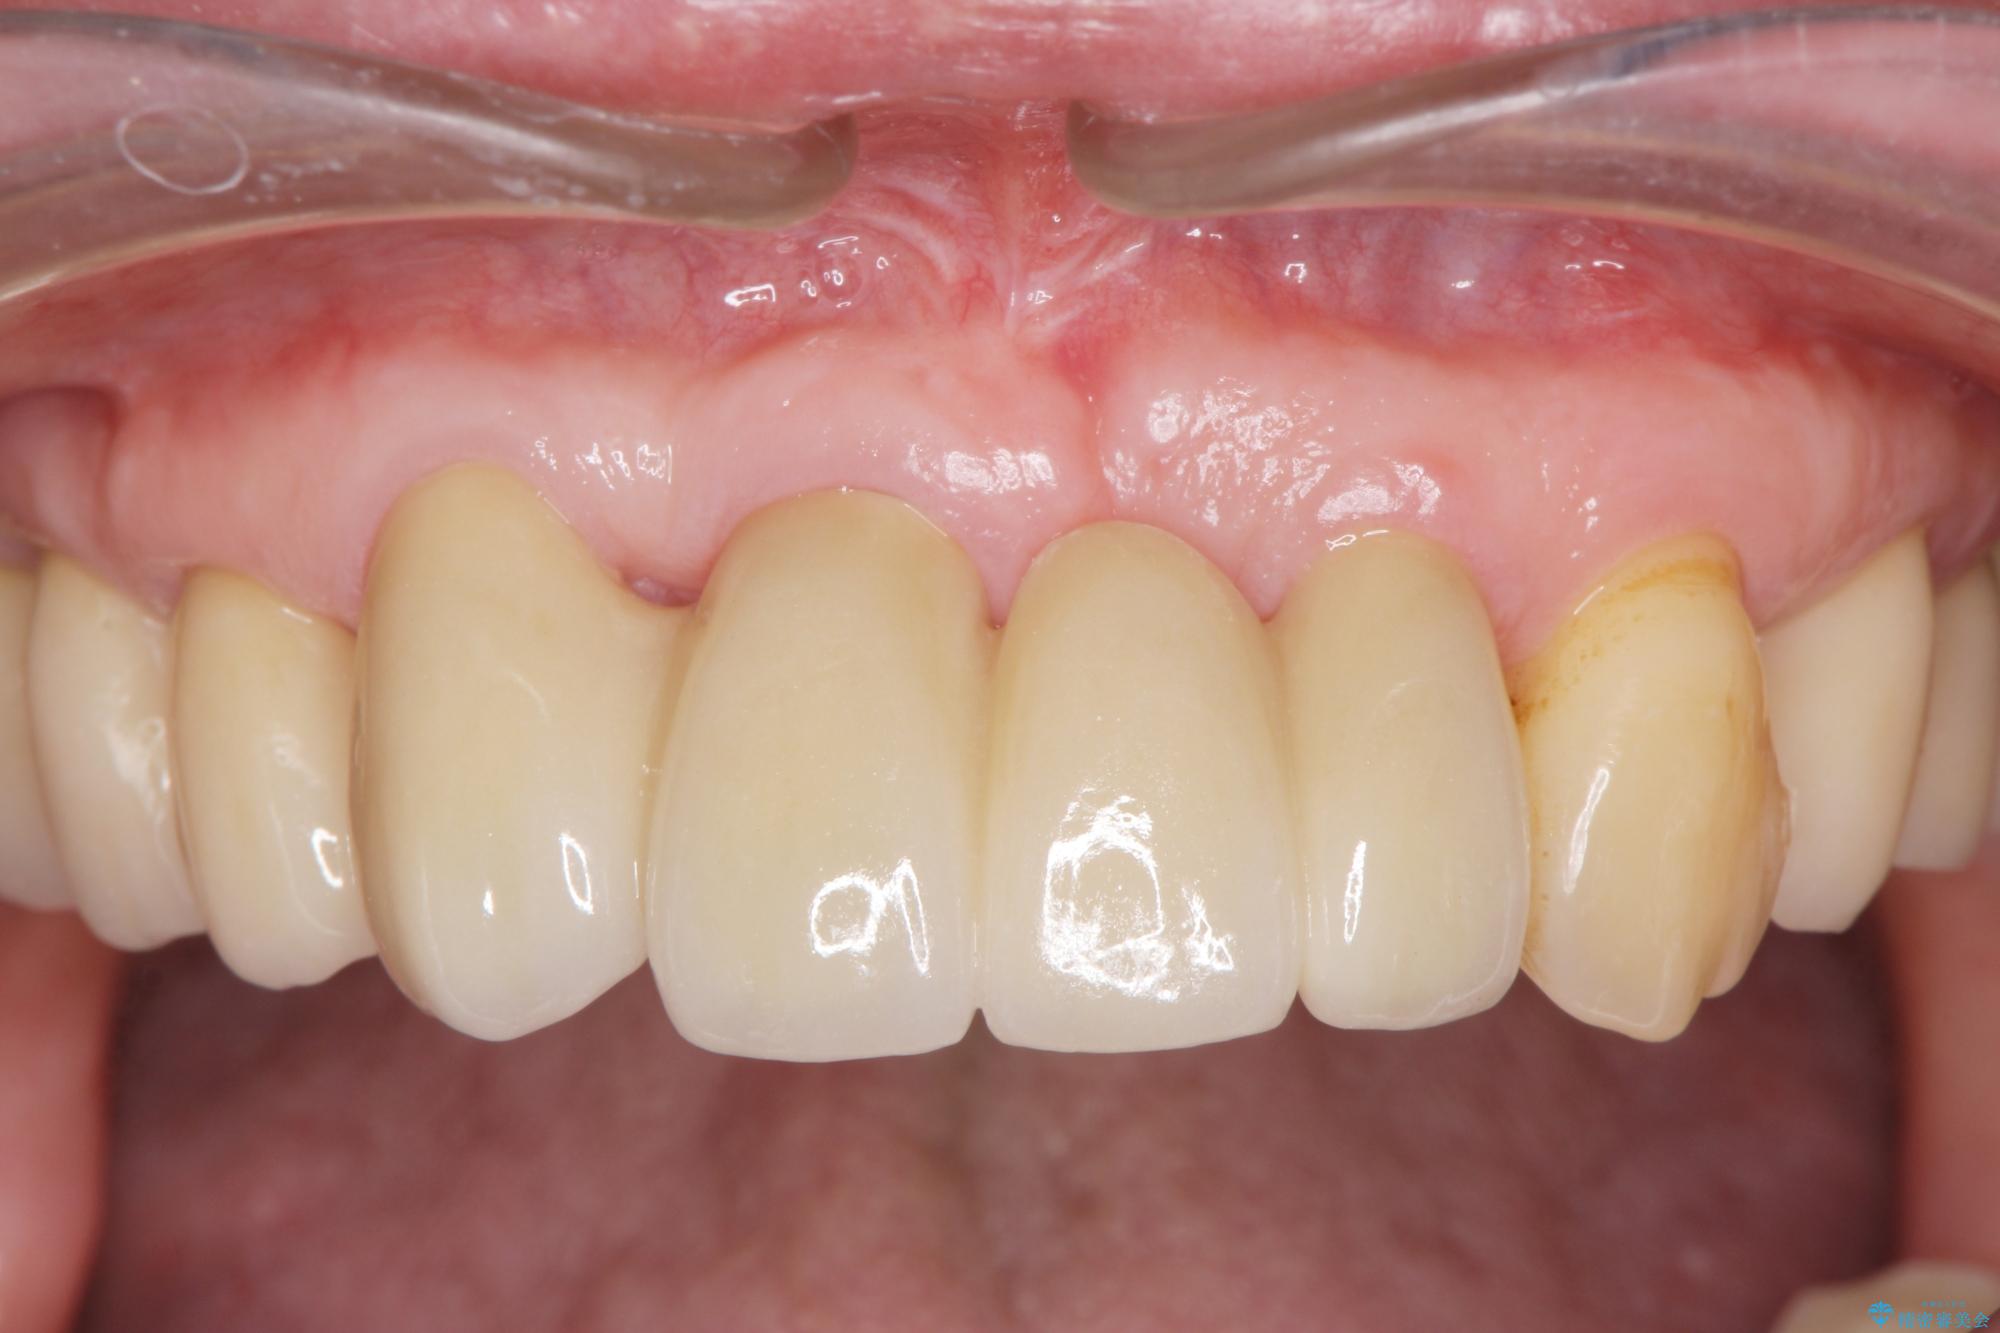

治療後

歯の総合的なマネージメントを行う包括的歯科治療の実践[ 歯周病・矯正・セラミック補綴 ] 治療後画像 歯の総合的なマネージメントを行う包括的歯科治療の実践[ 歯周病・矯正・セラミック補綴 ] 治療後画像 歯の総合的なマネージメントを行う包括的歯科治療の実践[ 歯周病・矯正・セラミック補綴 ] 治療後画像 歯の総合的なマネージメントを行う包括的歯科治療の実践[ 歯周病・矯正・セラミック補綴 ] 治療後画像

治療期間は長期間になりましたが、歯が非常に磨きやすくなり、見た目も改善したことで審美性を大きく改善することができました。